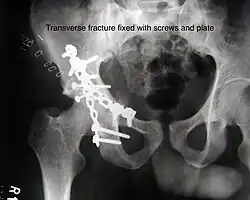

The final management depends on the size of the fragment(s), stability and congruence of the joint. In some cases traction for six to eight weeks may be the only treatment required; however, surgical fixation using screw(s) and plate(s) may be required if the injury is more complex. The latter treatment will be called for if bone fragments do not fall into place, or if they are found in the joint, or if the joint itself is unstable.

Innominate bone is a flat bone with many curves. In most part the bone is thick enough and has broad surfaces that are amenable to primary fixation using lag screw(s) and to neutralize forces across the bone one needs to add plate(s) on the surface of the fractured fragments for it to heal without deformity.

Implants : normally lag screws and reconstruction plates are preferred implants